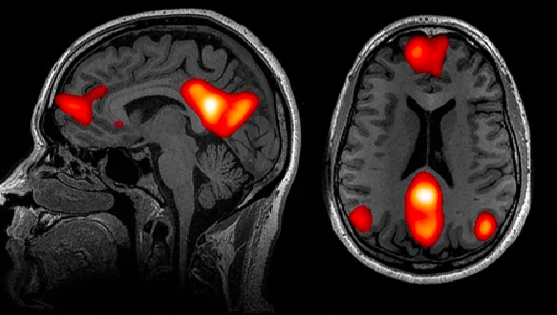

这项研究的结果在2020年发表在《自然通信》杂志上,揭示了默认网络中大脑孤独的热点。(default network)其中,这是大脑的一部分,当我们处于精神待机模式时,就会被激活。布兹多克说:“直到20年前,我们甚至不知道人类有这个系统。然而,研究发现,默认的网络活动占大脑能量消耗的大部分。

布兹多克及其团队解释说,默认网络的一些区域不仅更大,而且与大脑的其他部分有更强的连接。此外,默认网络似乎与许多人类进化出来的独特能力有关,如语言、预测未来和因果推理能力。一般来说,当我们想到别人的时候,默认网络会被激活,包括我们理解别人的意图。

人类大脑功能磁共振成像揭示了一些与默认网络相关的区域,当我们想到他人时,这些神经中心是最活跃的。

神经成像证据提供了默认网络连接的发现,支持心理学家之前的发现:孤独的人专注于社交白日梦,很容易怀旧过去的社会事件,甚至把自己的宠物拟人化,比如把自己的猫当人类说话,”布兹多克说。“这也需要默认网络来做。”